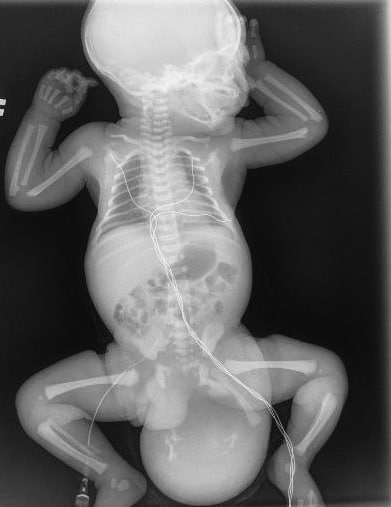

В Люберцах в Московский областной центр охраны материнства и детства поступила женщина на девятом месяце беременности. На скрининге были обнаружены врожденные пороки развития плода, а именно крестцово-копчиковая тератома. Эта опухоль представляет собой безболезненный узел, в котором могут находиться мышечная и костная ткани, а также волосы, зубы, глаза или конечности.

Мальчик весом 3230 граммов родился после кесарева сечения. Вес тератомы составил 650 граммов, то есть треть веса новорожденного. Образование прилегало к прямой кишке и сосудисто-нервному пучку маленького пациента. Вся анатомия ягодичной области была нарушена. Врачам пришлось по миллиметру выделять опухоль, ошибка могла привести к повреждению целостности кишки.

После операции образование отправили на гистологическое исследование. Выяснилось, что внутри находились элементы кишечной трубки, ткани поджелудочной железы, а также клетки волос и ногтей.